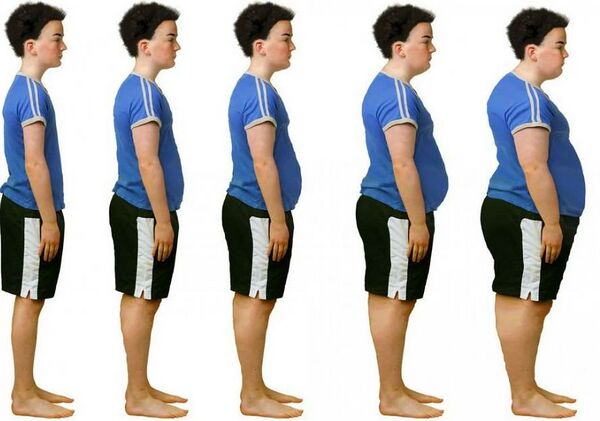

ترکیب بدنی

بدن از آب، پروتئین ، مواد معدنی و چربی تشکیل شده است .

یک فرد به طور بالقوه می تواند وزن یکسانی را حفظ کند اما نسبت هر یک از اجزای تشکیل دهنده بدن خود را به شدت تغییر دهد.

یک مدل دو جزئی از ترکیب بدن ، بدن را به جزء چربی و جزء بدون چربی تقسیم میکند.

چربی بدن (چربی ذخیره شده) بیش از حد می تواند استعداد ابتلا به بیماری های مزمن ، عوارض سلامتی و کمردرد را افزایش دهد.

مطالعات متعددی انجام شده است که ارتباط بین افزایش محتوای چربی و احتمال/شیوع کمردرد را برجسته کرده است.

مطالعه ای در سال۲۰۰۳ انجام شد نشان داد که یک رابطه مثبت متوسط بین چاقی و کمردرد وجود دارد.

با این حال نتایج بر اساس محاسبه BMI است که به طور قطعی محتوای چربی بدن را اندازه گیری نمی کند.

افزایش وزن بدن ، بیومکانیک و بارگذاری ستون فقرات را تغییر میدهد، و باعث ایجاد فشار اضافی برای وارد شدن به ساختارهای خاص میشود.

به عنوان مثال چاقی میتواند به تغییر وضعیت بدن مانند لوردوز(قوس) کمری شدید منجر شود که باعث تغییر در مکانیک بارگذاری ستون فقرات میشود.